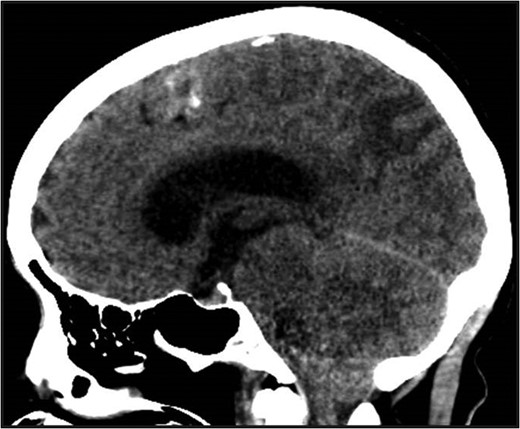

Non-contrast head CT. Non-contrast head CT showing hydrocephalus with tonsillar herniation and vasogenic edema of the parietal and occipital lobes.